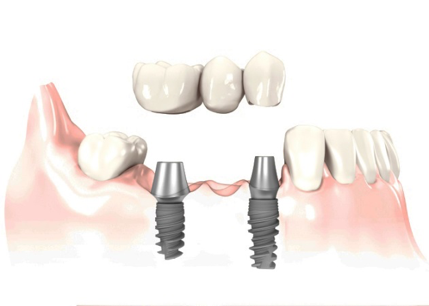

Puente sobre implante.

¿Cómo funciona¿ Anclando al hueso de la mandíbula dos implantes de titanio que harán la función de la raíz, dándole soporte a la masticación.

Una vez introducidos los implantes, se fijan las tres piezas dentales, fabricadas en metal y cerámica, igualando el color con los dientes vecinos para brindar un aspecto natural y saludable.

- (Si le faltan dos o más dientes)

- Implante fabricado en Titanio Grado V de la más alta pureza.

- Reemplaza la raíz del diente y evita la perdida de hueso.

- Indicado para adultos y tercera edad.

- Respaldo casa de implantes SIN